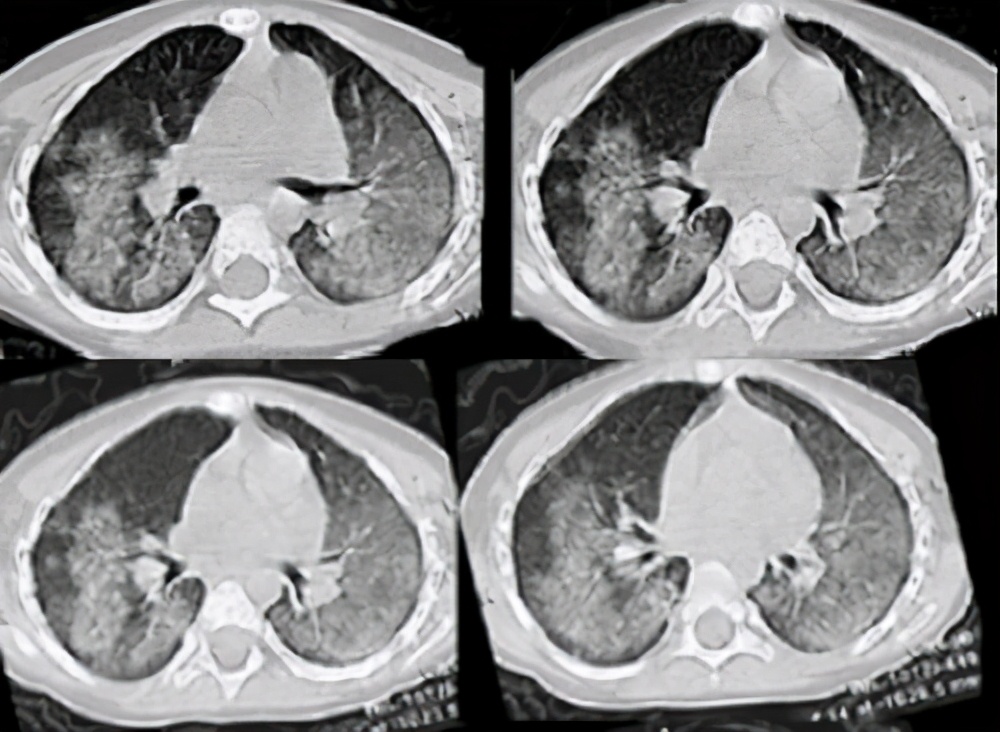

6、影像学检查

线型肺部弥漫性斑块浸润影,散于自肺门至肺外围,常可见肺尖部。肺部侵犯是肺部病变的特征之一。肺 x线的早期变化类似于肺水肿,咯血停止后短时间即可吸收。